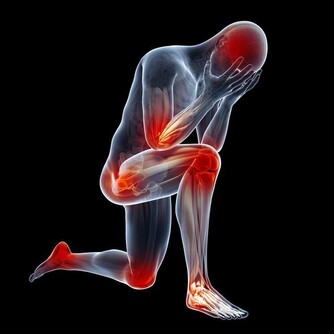

女人更年期症狀到來一般表現為:失眠、頻尿、腰酸背痛渾身不適,更年期婦女要當心,這些恐怕都是更年期症狀,需要就醫治療。

西紅柿專家表示由於更年期症狀多元,包含心悸、頻尿、失眠等,

因此多數婦女求助心臟科、泌尿科甚至精神科,而未能針對更年期問題治療。

他提出「3不5時」快篩法,「更年期婦女3不5時腰酸背痛、每晚頻尿如廁超過3次,

每週3天睡眠不超過5小時,有任一症狀就該尋求婦產科醫師診治。」